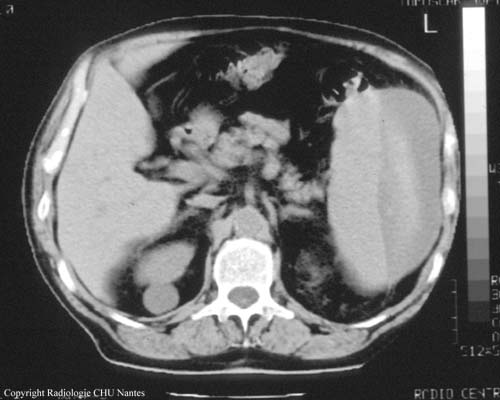

HÉMATOME SOUS-CAPSULAIRE